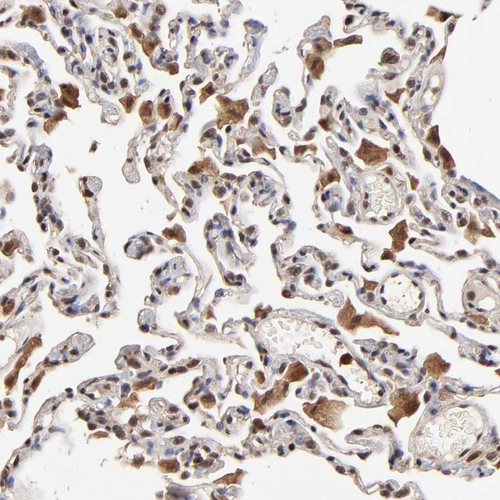

Immunohistochemical staining of human small intestine shows strong cytoplasmic positivity in glandular cells.